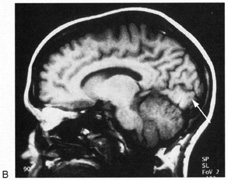

Fig. 15. Bilateral incomplete hemianopia. A 69-year-old man with decreased vision after prostate surgery. A. Fields show remaining central parafoveal vision with some sparing of inferior left quadrant. Note how the defect respects the vertical meridian. B. MRI shows bilateral medial occipital infarction, with sparing of the occipital poles, accounting for the macular-sparing bilaterally. (Courtesy of Dr. Lucia Vaina.)

Bilateral lesions of striate cortex are not rare. Focal midline lesions such as tumors or traumatic injury may affect both striate cortices concurrently, because the right and left striate cortices face each other on the medial occipital surface. The most common cause, however, is posterior circulation ischemia.57 This can affect both striate cortices either simultaneously or sequentially,57 because the right and left posterior cerebral arteries have a common origin from the basilar artery. Twenty-two percent of patients with a unilateral occipital infarction develop bilateral infarction over 3 years.58 Bilateral incomplete hemianopia is distinguished from bilateral optic nerve or ocular disease by the high congruity of the visual fields and step defects along the vertical meridian which indicate the hemifield nature of the visual loss (Fig. 15).57 Such steps are important to seek with a skilled perimetrist, but even so they can be difficult to demonstrate with bilateral hemiscotomata from occipital pole lesions.59 Bilateral quadrantanopias can occur,47,48 often in patients with prosopagnosia and achromatopsia for example, and may mimic the altitudinal defects of optic neuropathy.